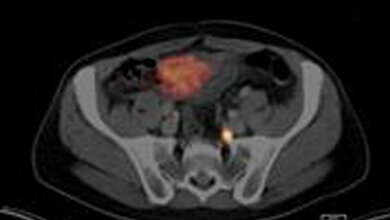

„Die Bereiche in der Prostata, in denen Tumore vermutet werden, sind vergleichsweise klein. Sie mussten umständlich über ein manuelles Führungssystem angezielt werden“, beschreibt der UKL-Radiologe die bisherige Prozedur. „Der Patient liegt bis zu einer Stunde bäuchlings im MRT, besonders die zweite Hälfte der Prozedur wird von vielen Patienten als belastend empfunden.“